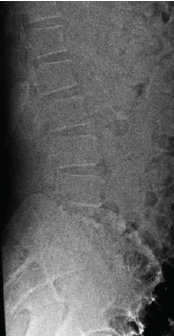

Post-operative Microdiscectomy Complicated by Lumbar Epidural Hematoma with Cauda equina Syndrome Following Dual Viral Infection: A Rare Case Report and Its Management